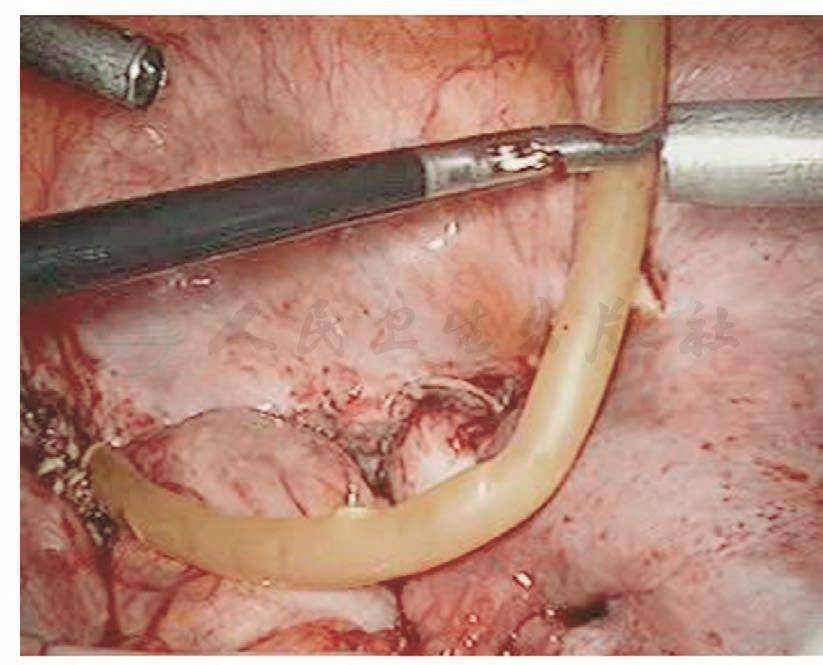

膀胱破裂后,术中能及时发现并修补,预后比较理想。以往凡是膀胱破裂基本都是中转开腹并由泌尿大夫修补,现在妇科大夫基本已掌握了膀胱破裂修补的技巧,而且腹腔镜下的操作技巧也比较娴熟,所以膀胱破裂后的修补基本都是由妇科内镜医生进行。膀胱裂口的位置决定修补的难度,膀胱前壁及侧壁相对容易,而后壁相对难度较大。膀胱裂口缝合后的愈合与缝合的方法密切相关。以前修补膀胱裂伤是采用不吸收的缝线,所以最主要的问题是怕缝线穿透了膀胱黏膜,引起术后膀胱结石,现在采用的是可吸收缝线,术后引起膀胱结石的问题已得到了解决,只要组织层正确对合,裂伤可以愈合。缝合前先将裂口两侧的膀胱黏膜边缘适当修剪齐,缝合时用5-0可吸收线从距离膀胱裂口边缘约5mm进针,穿过黏膜层,镜下打结后连续缝合黏膜层,再用3-0可吸收线8字形缝合膀胱肌层(图103~图110)。修补膀胱破裂口时必须要注意:

图103 膀胱裂口边缘进针

图104 膀胱黏膜前进针

图105 裂口中间黏膜前进针

图106 缝合对侧黏膜层

图107 缝合裂口对侧边缘

图108 封闭破裂口

图109 缝合前浆肌层

图110 修补后的创面